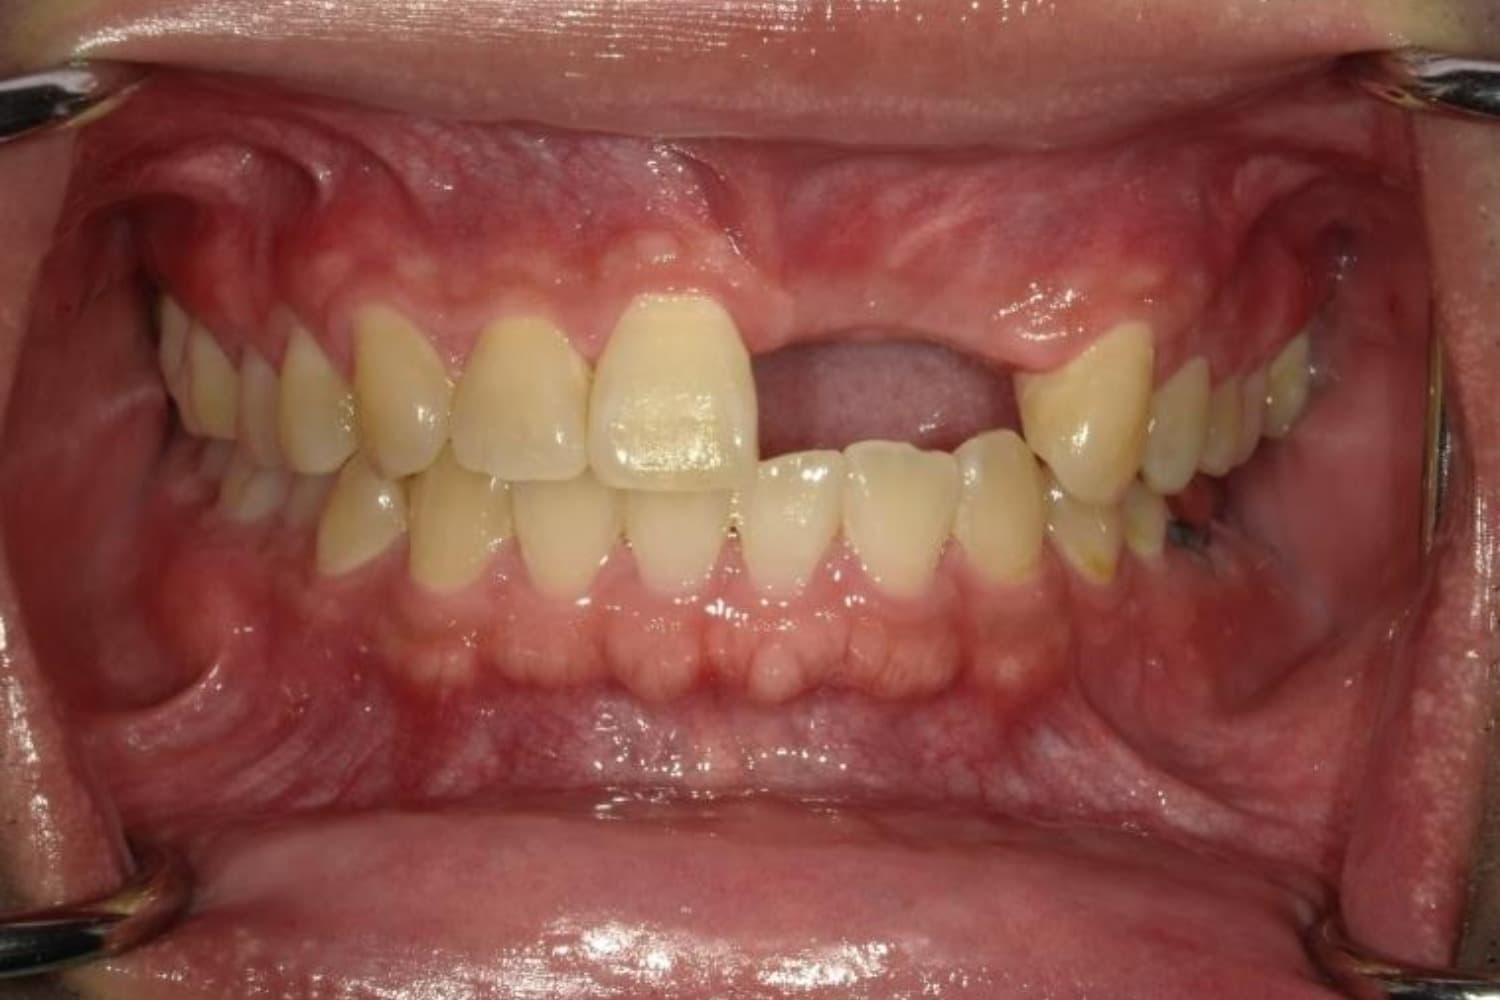

ガタガタとした歯並びや八重歯(1)

Before

ガタガタとした歯並びや八重歯をマウスピース矯正(インビザライン)にて治療

主訴

下の前歯のガタガタが気になる

治療期間

2年5カ月

費用

90万円